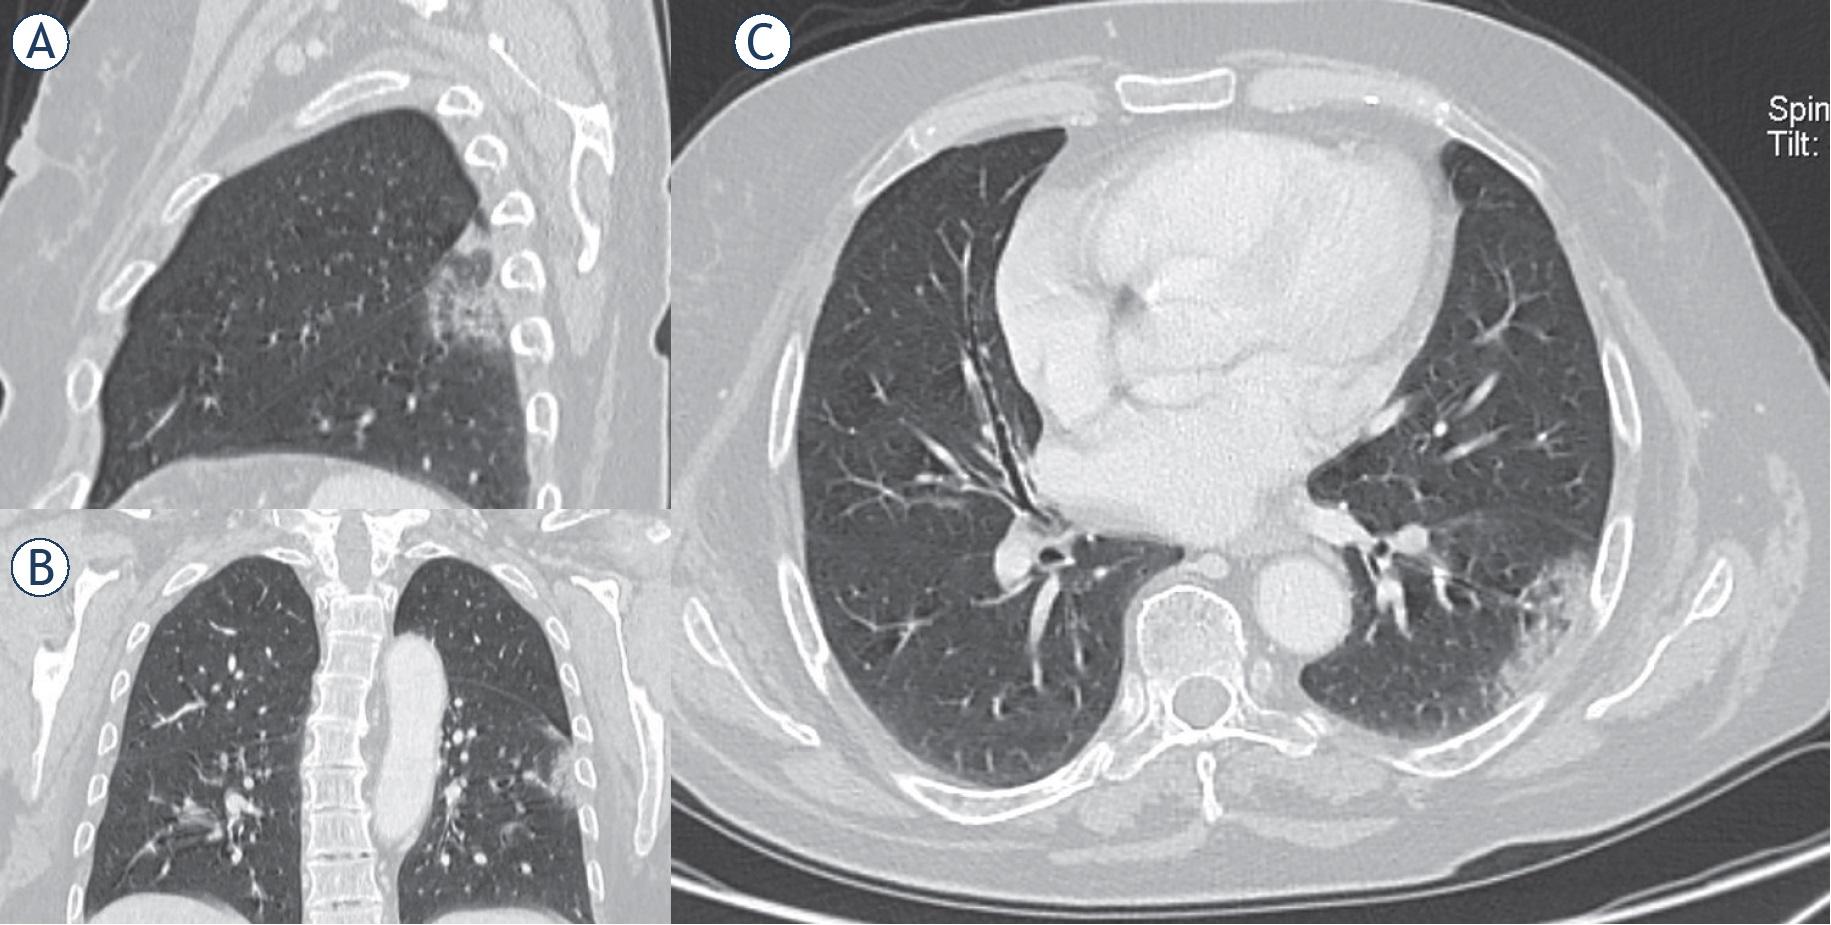

Woman, 54 year. CT shows patchy consolidation in apical segment of left lower lung. (A) Multiplanar reconstruction in sagittal plane; (B) multiplanar reconstruction in coronal plane; (C) axial plane.

Dissipation stage. Two and 3weeks after the onset of clinical symptoms. “CT shows patchy consolidation or strip-like opacity. As time goes on, it showed grid-like thickening of interlobular septa, thickening and strip-like twist of bronchial walls and a few scattered patchy consolidations”7 (Figure 5).

Man, 76 year. CT shows strip-like opacity, grid-like thickening of interlobular septa, thickening and strip-like twist of bronchial walls and patchy consolidations. (A) Axial plane; (B) multiplanar reconstruction in coronal plane; (C) multiplanar reconstruction in sagittal plane.